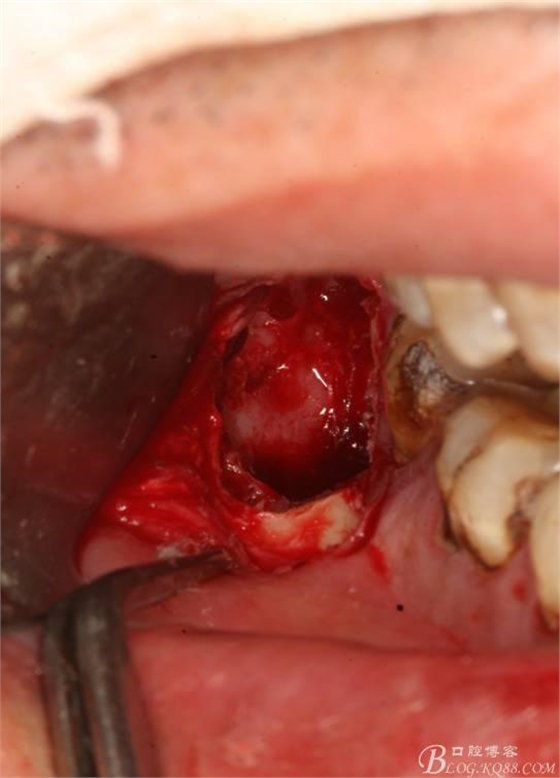

8.清理拔牙創(chuàng)

9.縫合